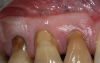

A male patient in his 30s presented for treatment of increasing recession he had had over his lifetime. Upon examination, a complete lack of gingiva on the facial of tooth No. 6 was observed. Although he had about 1.5 mm of gingiva on the facial of tooth No. 7 (Figure 4), both teeth probed to 3 mm. This indicated an absence of attached gingiva on the facial of these teeth in addition to increasing recession.

With a low lip line, the patient was not concerned about esthetics, and he was not experiencing root sensitivity. It was determined and agreed that a FGG was the best option for him in order to increase the amount of gingiva and limit further recession.

Fig 4. Patient presented with no gingiva on tooth No. 6 and 1.5 mm of gingiva on tooth No. 7 with increasing gingival recession. Probing of each tooth to 3 mm indicated a lack of attached gingiva.